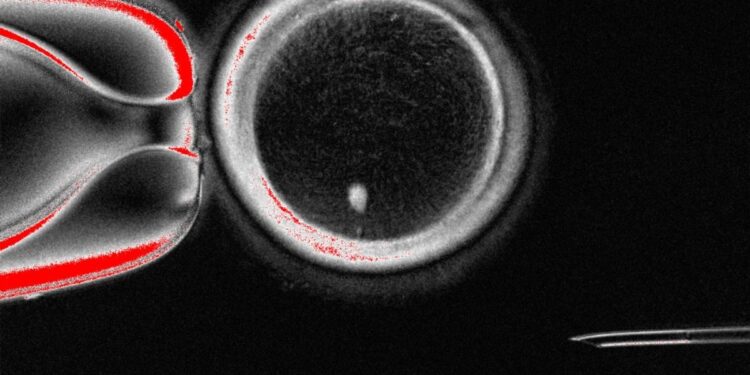

방추사(spindle. 흰 점)가 있는 인간 체세포 핵이식(SCNT) 난자 [Mitalipov laboratory 제공. 재판매 및 DB 금지]

환자의 체세포(피부세포) 핵을 핵이 제거된 기증 난자에 이식(체세포 핵이식. SCNT)해 정상적으로 수정 가능한 난자를 만들고, 이를 정자와 수정해 배반포기까지 배양하는 데 성공했다.

이들은 이 연구에서 사람 피부세포의 핵을 핵이 제거된 난자에 삽입한 다음 정자와 수정시키면서 전기 자극과 약물(roscovitine) 투여해 체세포 염색체가 절반으로 줄어들게 하는 체세포 감수분열을 일으켰다.

연구팀이 이렇게 만든 체세포 핵이식 수정란을 배양한 결과 일부는 4~10세포기까지 발달했으며, 약 9%는 수정 6일째 배반포 단계까지 발달했다.